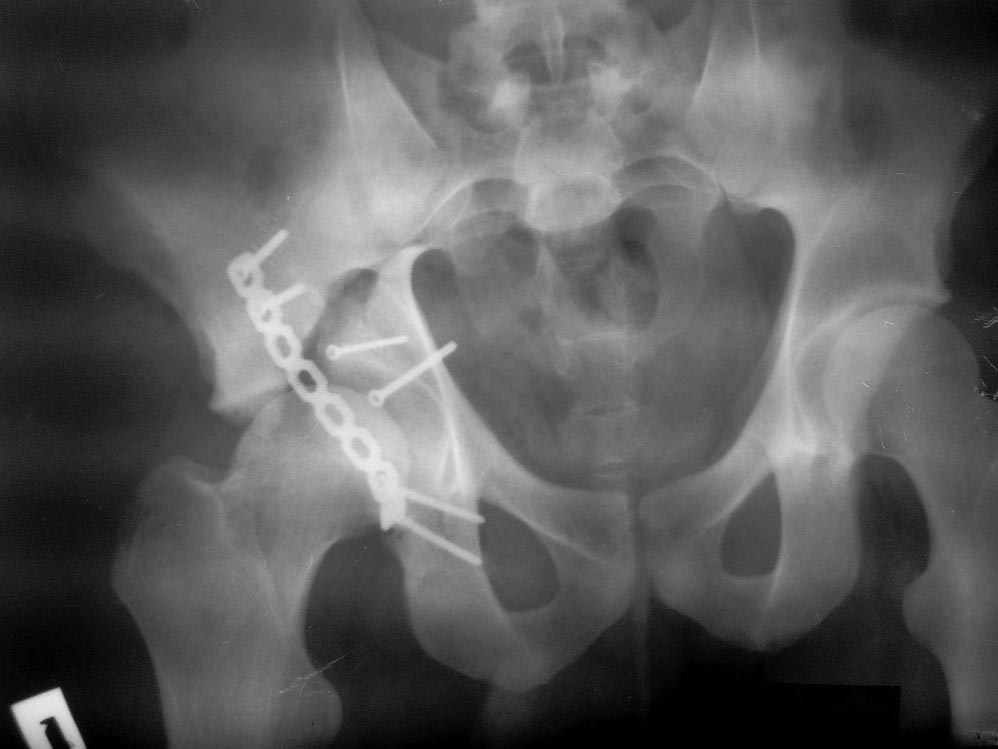

Пациент 19 лет, ДТП в сентябре 2012 г, оперирован поэтапно в др. клинике. В сентябре пациенту первым этапом была проведена операция – МОС лодыжек правой голени, МОС правой бедренной кости. Через 2 недели была проведена операция МОС костей таза и открытое устранение вывиха правого бедра.

Повторная операция – реостеосинтез костей таза была проведена через 1 месяц после первичной. Дз: задний вывих правого бедра (сроки -3 месяца). Асептический некроз головки правой бедренной кости. Неконсолидирующийся перелом средней трети правой бедренной кости, неправильно консолидирующийся перелом лодыжек правой голени с подвывихом стопы кзади, передняя медиальная нестабильность правого К/С. Сгибательно-приводящая контрактура правого Т/Б сустава, сгибательно-разгибательная контрактура правого К/С, эквинусная установка в правой стопе на фоне пост-операционного пареза

Перелом вертлужной впадины отличается от “переломов таза” не только исследованием, но также тактикой. По классификации Летурнеля расположение линии перелома характерно для поперечного перелома вертлужной впадины, но наличие шурупов в заднем крае (второй снимок) и вывих бедра подтверждают, что здесь сочетание заднего края с поперечным переломом.

Через задний доступ смогли сделать частичную репозицию, а здесь напрашивался двойной доступ спереди и сзади. Репозиция в положении на боку затруднительна, и вытяжение за перекладину над операционным столом облегчило бы репозицию.